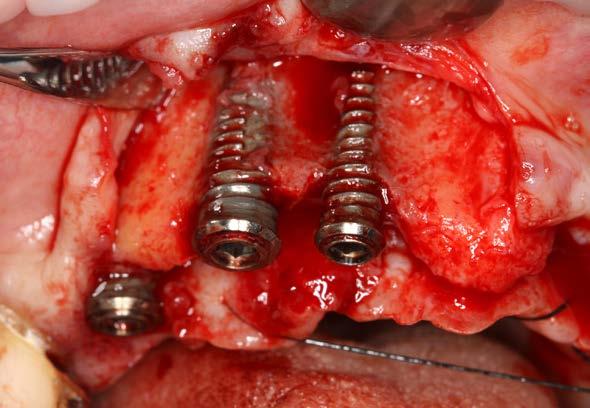

Figuras 4 y 5. Exposición de colgajos del arco superior con los implantes completamente expuestos sin tabla vestibular, afectados por periimplantitis.

190. Junio 2024 15